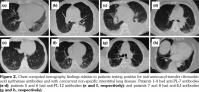

Table 4 contains detailed information (anti-ARS antibody status, age, sex, MTX and bDMARDs treatments, anti-CCP, and RF values) for patients who tested positive for anti-ARS antibody and had also ILD. MTX was administered to one patient while bDMARDs were administered to three patients. Abatacept and etanercept were administered to two and one patients, respectively. Except for one patient who tested positive for anti-PL-7 antibody, anti-CCP antibody and RF titers were high. Chest CT revealed that these patients did not have PM/DM during the clinical course of the disease (Figure 2). Chest CT scans revealed non-specific interstitial pneumonia lung complications in all patients. No characteristic changes were associated with the respective anti-ARS antibodies detected in patient sera. Moreover, patients with rapid progression of lung complications were absent.